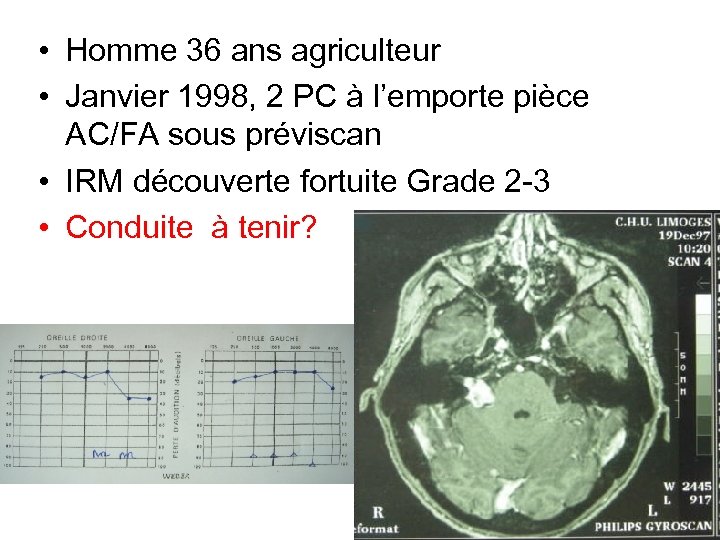

• Homme 36 ans agriculteur • Janvier 1998, 2 PC à l’emporte pièce AC/FA sous préviscan • IRM découverte fortuite Grade 2 -3 • Conduite à tenir? Déc 97

• Homme 36 ans agriculteur • Janvier 1998, 2 PC à l’emporte pièce AC/FA sous préviscan • IRM découverte fortuite Grade 2 -3 • Conduite à tenir? Déc 97